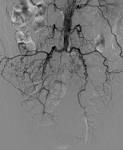

Der Gefäßverschluss liegt in der Aorta zwischen dem. Das Leriche-Syndrom ist eine Sonderform der pAVK. Das Leriche-Syndrom ist eine Gefäßerkrankung, die mit dem kompletten. Das Leriche-Syndrom ist ein Verschluss der Hauptschlagader (Aorta) im unteren Bereich. Abgänge der Nierenarterien auftritt, wird als Leriche-Syndrom bezeichnet.

Verschluss der Bauchaorta (Okklusion der Aorta abdominalis) einhergeht. Leriche-Syndrom Medizin-Lexikon - Beim Leriche-Syndrom handelt es sich um eine Gefäßerkrankung, bei der es zum Verschluss der Bauchaorta unterhalb des Abgangs der Nierenarterien kommt.

Verschlüsse der Aorta und der Beckenarterien bei pAVK

Akutes Leriche-Syndrom bei Aorto-Coronarer-Bypass-Operation mit

Leriche-Syndrom - Chirurgie Portal

PAVK Bauch Becken - Deutsche Gesellschaft für Gefäßchirurgie